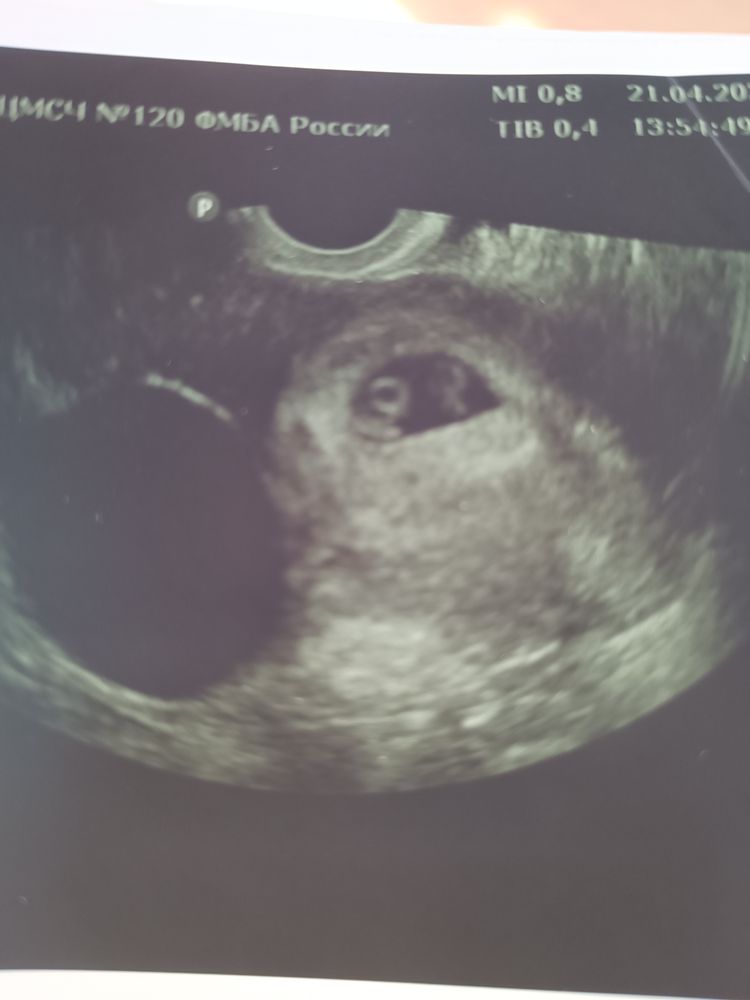

6,5 недель